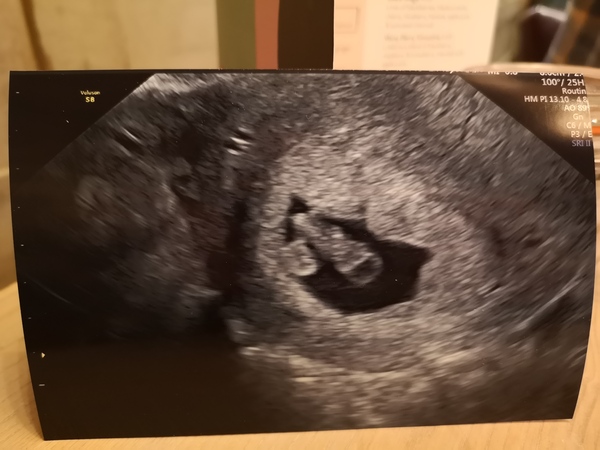

EmilyJ1234 · 27/01/2020 20:31

This is mine back from 8+4 and could see little heart beating away. We were really lucky to get such a lovely pic, 12 and 20 week ones were rubbish as he/she was moving so much! xxx